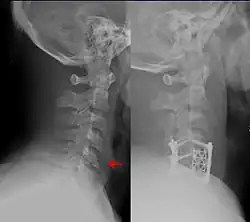

![]() A fracture of the lower cervical vertebrae, one of the conditions treated by orthopedic surgeons and neurosurgeons | |

Orthopedic surgery or orthopedics (alternative spelling orthopaedics) is the branch of surgery concerned with conditions involving the musculoskeletal system.[1] Orthopedic surgeons use both surgical and nonsurgical means to treat musculoskeletal trauma, spine diseases, sports injuries, degenerative diseases, infections, tumors and congenital disorders.